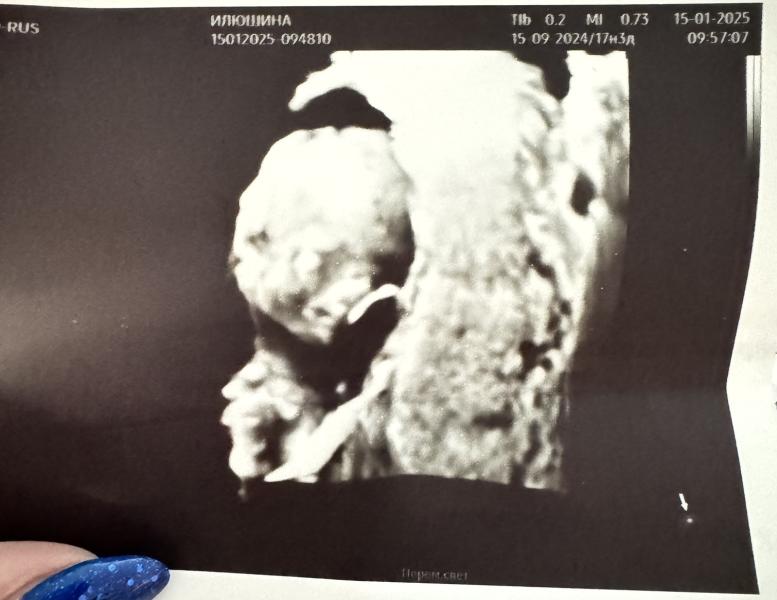

15 недель 1 день

Моя маленькая улыбака🥰

По узи сегодня 15 недель 4 дня

Вес - 108 грамм